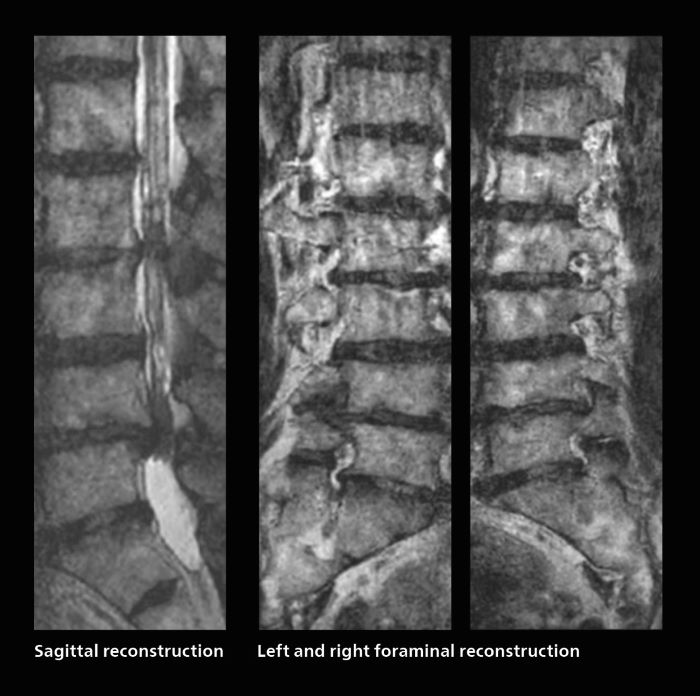

Faster lumbar spine exams are beneficial for patients with pain

Many patients who must undergo a lumbar spine examination suffer from back pain. For these patients it is difficult to maintain the imaging position long enough to successfully complete the examination. “In such cases, using SmartSpeed allows us to perform volume imaging, so that we acquire only one high resolution 3D sequence in a short time and then reconstruct the other orientations from that,” Dr. Katahira says.

“This is highly advantageous because the patient needs only endure a short exam time, whereas before it was necessary to acquire a larger number of sequences in total. We have seen that the shorter time has allowed us to scan patients who previously could not finish the exam. This is a great advantage.”

Fast lumbar spine imaging for successful exam of patient in pain

A patient arrived saying that undergoing MRI was not possible because of severe back pain and leg pain, was imaged with SmartSpeed in only 94 seconds. The scan was diagnostic and afterwards the patient confirmed that it only took a little while. Performed on Elition X.

Fast lumbar spine MRI with SmartSpeed of a patient in pain produced a successful isotropic diagnostic scan in only 94 minutes.

The hospital’s fast lumbar spine ExamCard includes T2W SpineVIEW, 1:40 min, 1.0 mm isotropic, acceleration factor 12.